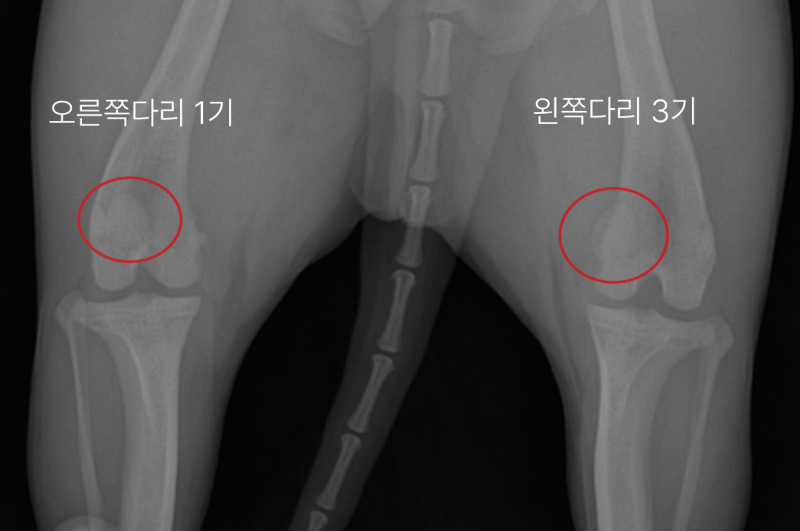

환자의 뒷다리 방사선 사진 / 환자의 왼쪽 다리 세부 사진

환자의 방사선 사진입니다. 오른쪽 다리는 1기, 왼쪽 다리는 슬개골 탈구 3기 진단을 받았습니다.

사진에 보시면 왼쪽 다리의 경우 정상 위치(무릎의 중앙)에 있어야 할 슬개골이 내측으로 빠져있는 것을 볼 수 있습니다.

아직 슬개골 탈구가 1기인 오른쪽 다리는 무릎의 중앙에 위치하고 있는 것을 비교하여 볼 수 있습니다.